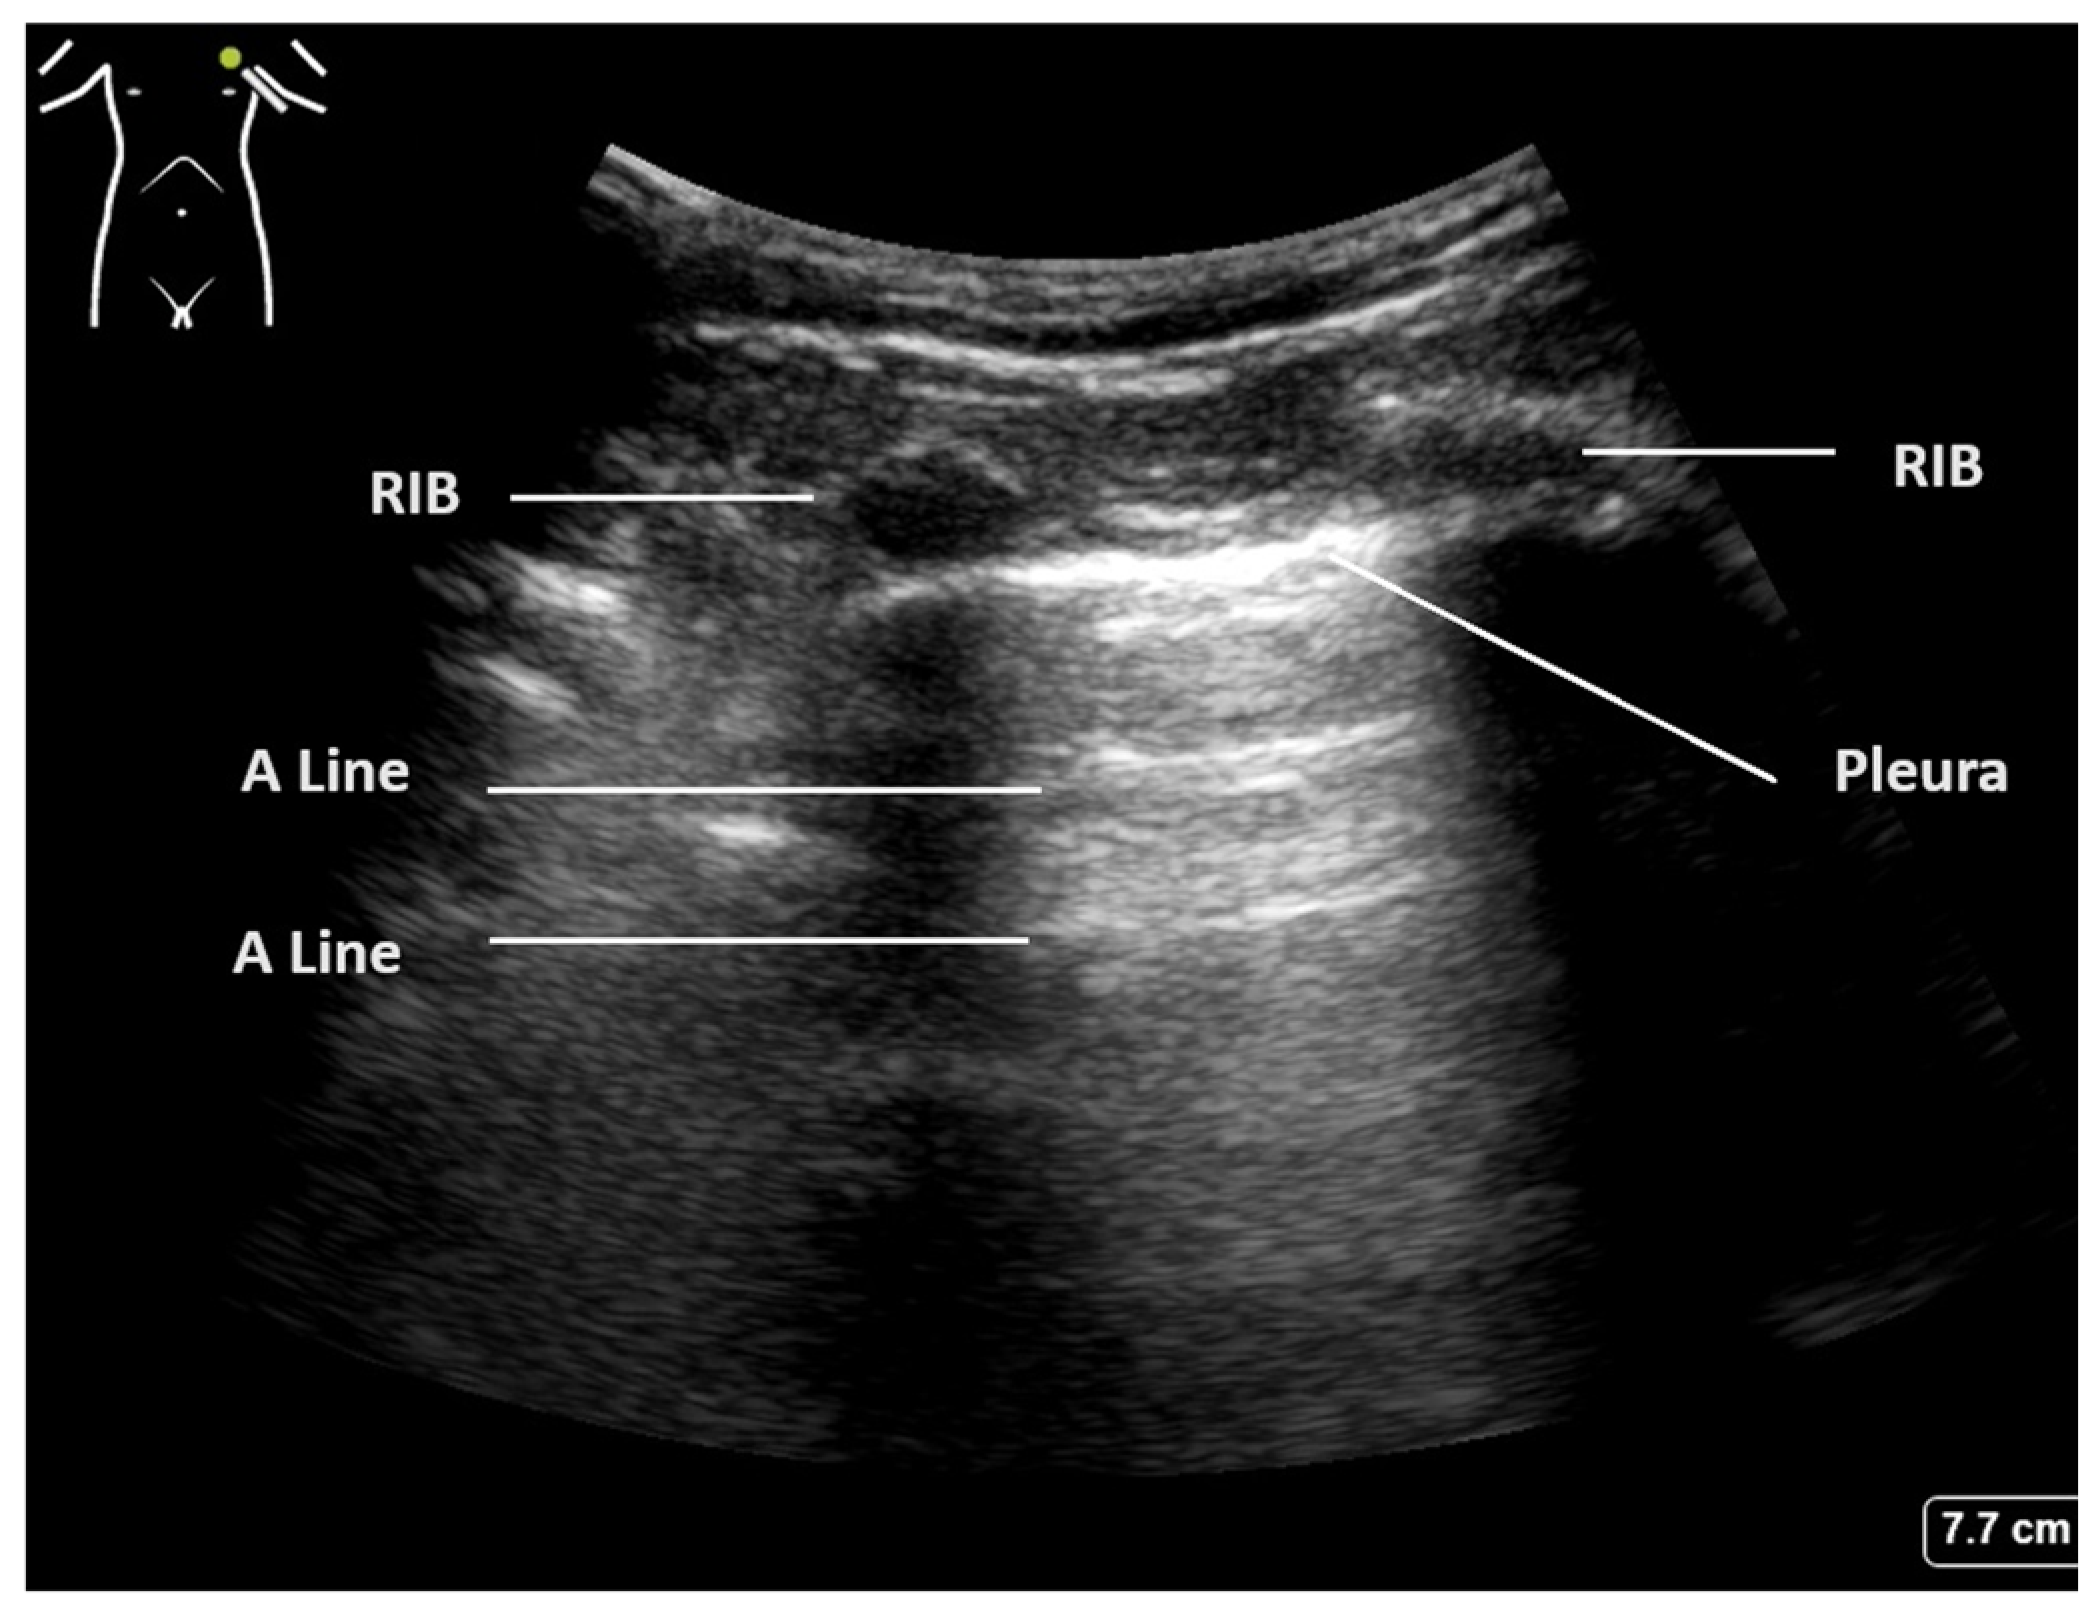

The crucial diagnostic signs in LUS are related to the artefacts generated by the subcutaneous tissues and the air beneath. Beginning with Brightness mode (B-mode), the normal findings are demonstrated in Figure 1. With the lung centred in the middle of the image, the soft tissues and ribs can be seen, with the bright white pleural line located approximately 0.5 cm below. The ‘bat sign’ is useful analogy to help identify the correct probe position, as the ribs cast a shadow at the bottom of the image, with the pleura identifiable in between.

Figure 1.

Normal lung ultrasound of aerated lung demonstrating ’bat wing’ appearance of ribs and A-lines.

The parietal and visceral pleura can be seen as a bright white line between the rib spaces. This pleural line can be seen to be sliding with tidal ventilation, creating a shimmering movement artefact that is suggested to be reminiscent of ants walking on a tree branch. This line represents the interface between the soft tissues of the chest wall and the aerated lung beyond. The pleura itself is thin and smooth in a normal aerated lung, and changes to this pleural line indicate potential pathology [2,20].

Below the pleural line and within normal aerated lung, a ring-down artefact termed A-lines can be visualised. These artefacts emanate from the pleura itself when it is thin and dry, allowing the observer to infer its existence. The pleura reflects some of the ultrasound beam back towards the transducer, and this, in turn, is reflected back to the pleura. Once reflected to the probe, a line is produced at the same distance below the pleura as the probe is above it. This artefact is often seen repeated below the pleural line at multiples of the probe–pleural distance, as sound waves are reflected back and forth, and signifies air. The presence of A-line artefacts, coupled with pleural sliding, indicates normal aerated lung [1].